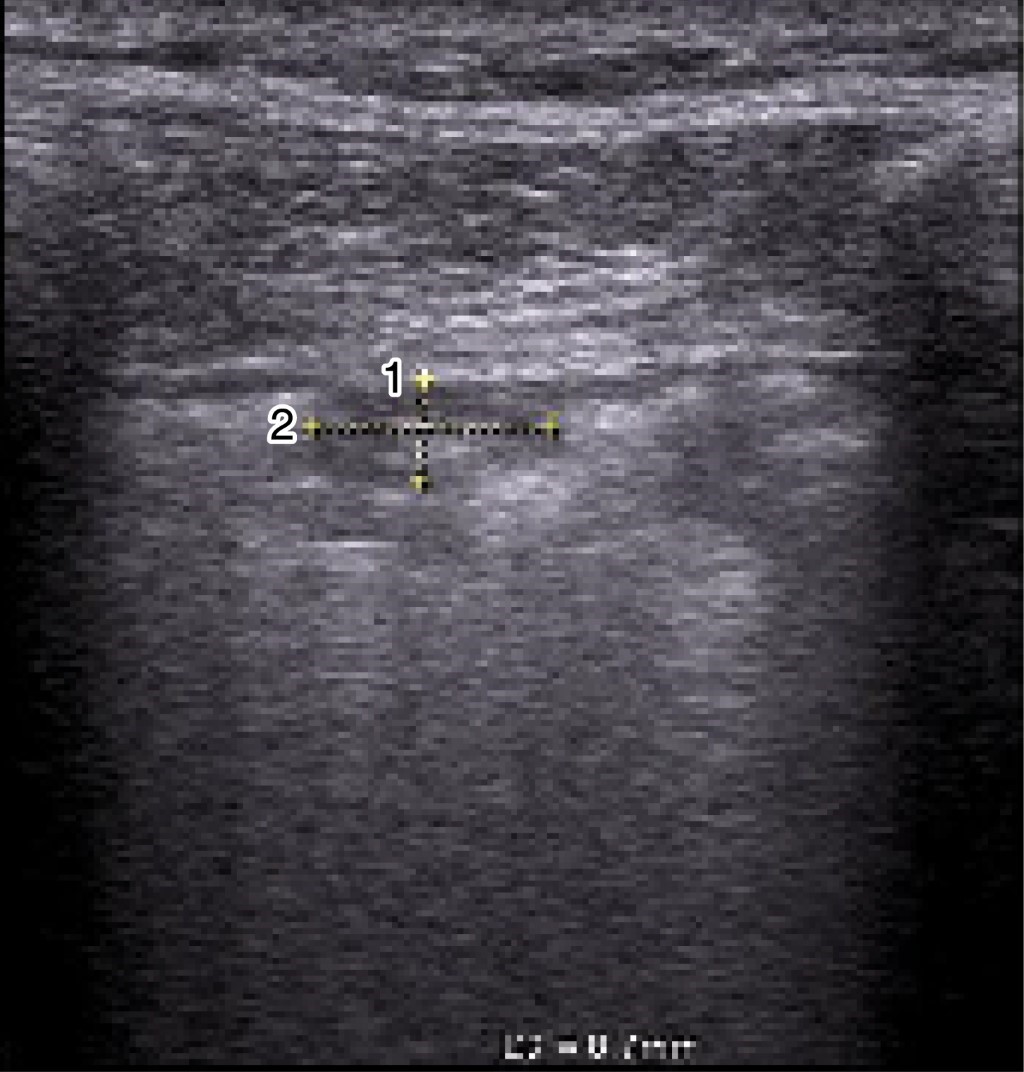

Posterior a la identificación de la consolidación subpleural en modo B (Figuras 1 y 2) se realizará la medida del tamaño de ésta en modo M, colocando el marcador al centro de la consolidación y se procederá a evaluar el movimiento respiratorio cíclico del pulmón y posteriormente se congelará la imagen al observar por lo menos dos movimientos cíclicos y se procederá a la medición al final de la espiración, en sus medidas longitudinal y transversal, colocando el cursor para su medida en mm (Figuras 3 y 4).

Las consolidaciones subpleurales se identificaron como lesiones hipoecoicas localizadas en la región subpleural, para ser más específicos por debajo de la pleura, o bien descritas como "signo de la pleura cortada", las cuales presentan cambios en su tamaño a la inspiración y espiración.

La técnica que proponemos es medir dichas consolidaciones principalmente en modo M, ya que en modo B no se pueden identificar claramente los bordes de la consolidación, lo cual dificulta la medición durante la inspiración y espiración, siendo este último el valor que se tomará en cuenta, como se observa en las imágenes.

Figura 1